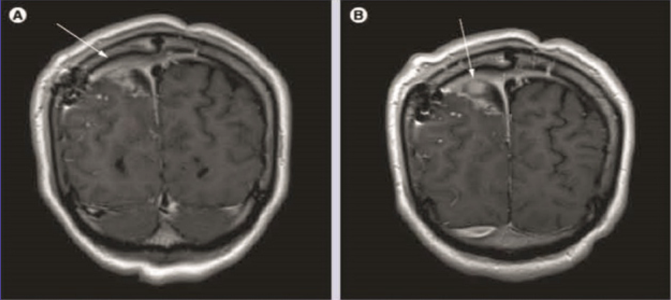

Gadobutrol (A & B) contrast - enhanced spin-echo T-weighted coronal brain images in a patient with brain tumor and postsurgical changes. shows dural enhancement ( A, arrow) at the right and left of the tumor with the presence of nodular area of enhancement ( B, arrow) (A & B) show a better degree of enhancement and internal morphology.